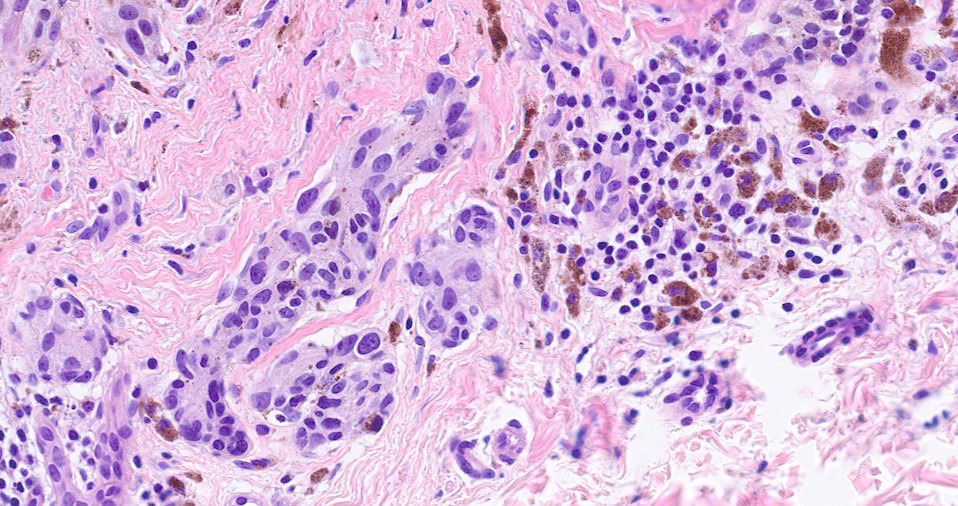

Histological features

•Heavy pigmentation (sometimes gray/green)

•Variable atypia (can be marked)

•Central pagetoid spread

•Superficial dermal atypia

Most important is melanoma. Distinction is best afforded by the site of the nevus and the patient’s age. Vulval melanoma is generally a tumor of the elderly. Atypical genital nevus occurs in girls and young women.

There can be overlap with dysplastic nevi although the typical architecture of the latter is absent. Large, heavily pigmented, dyscohesive nests with a retraction artifact point towards atypical genital nevus. Knowing the site of the nevus is all important.